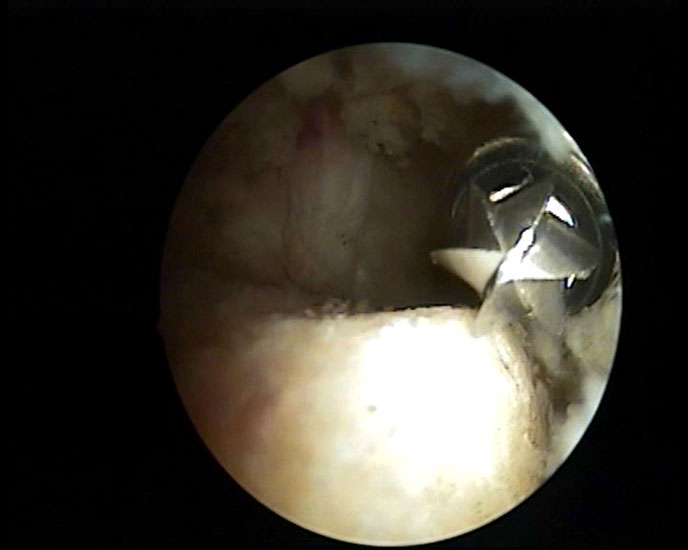

Abbildung 5-7, Video 2

Zunächst wird die Bursektomie (Abb. 5: gerötete Bursa subachillea; C=Calcaneus, B=Bursa, AS=Achillessehne) mit der Radiofrequenzsonde durchgeführt und die Haglundexostose dargestellt. Alternativ kann die Bursektomie mit einem Shaver durchgeführt werden. Hierbei sollte der Ansatz der Achillessehne kaudal einsehbar sein (Abb. 6: C=Calcaneus, AS=Achillessehne) und unbedingt die gesamte mediolaterale Ausdehnung der posterioren Calcaneusfläche erfasst werden (Abb. 7). Häufig liegen Anteile der Exostose weit medial und/oder lateral und werden übersehen.

Nach vollständiger Darstellung erfolgt die Resektion der Exostose mit einem Acromionizer von medial, wobei auch hier die geschlossene Seite des Arbeitsansatzes zum Schutz der Achillessehne nach dorsal ausgerichtet werden sollte. Verwendet werden können wahlweise Kugel-, Zapfen- oder Walzenansätze mit 3,5-5,5 mm Durchmesser. Ein kleinerer Durchmesser vereinfacht zwar das Handling im engen retrocalcanearen Raum, erfordert aber einen höheren zeitlichen Aufwand als die Verwendung einer höherkalibrigen Fräse. Der Knochenabrieb verstopft dünne Instrumente häufig und der Durchfluss der Spülflüssigkeit ist gering. Es hat sich bewährt, zwei verschiedene Größen bereitzuhalten und ggf. intraoperativ zu wechseln.